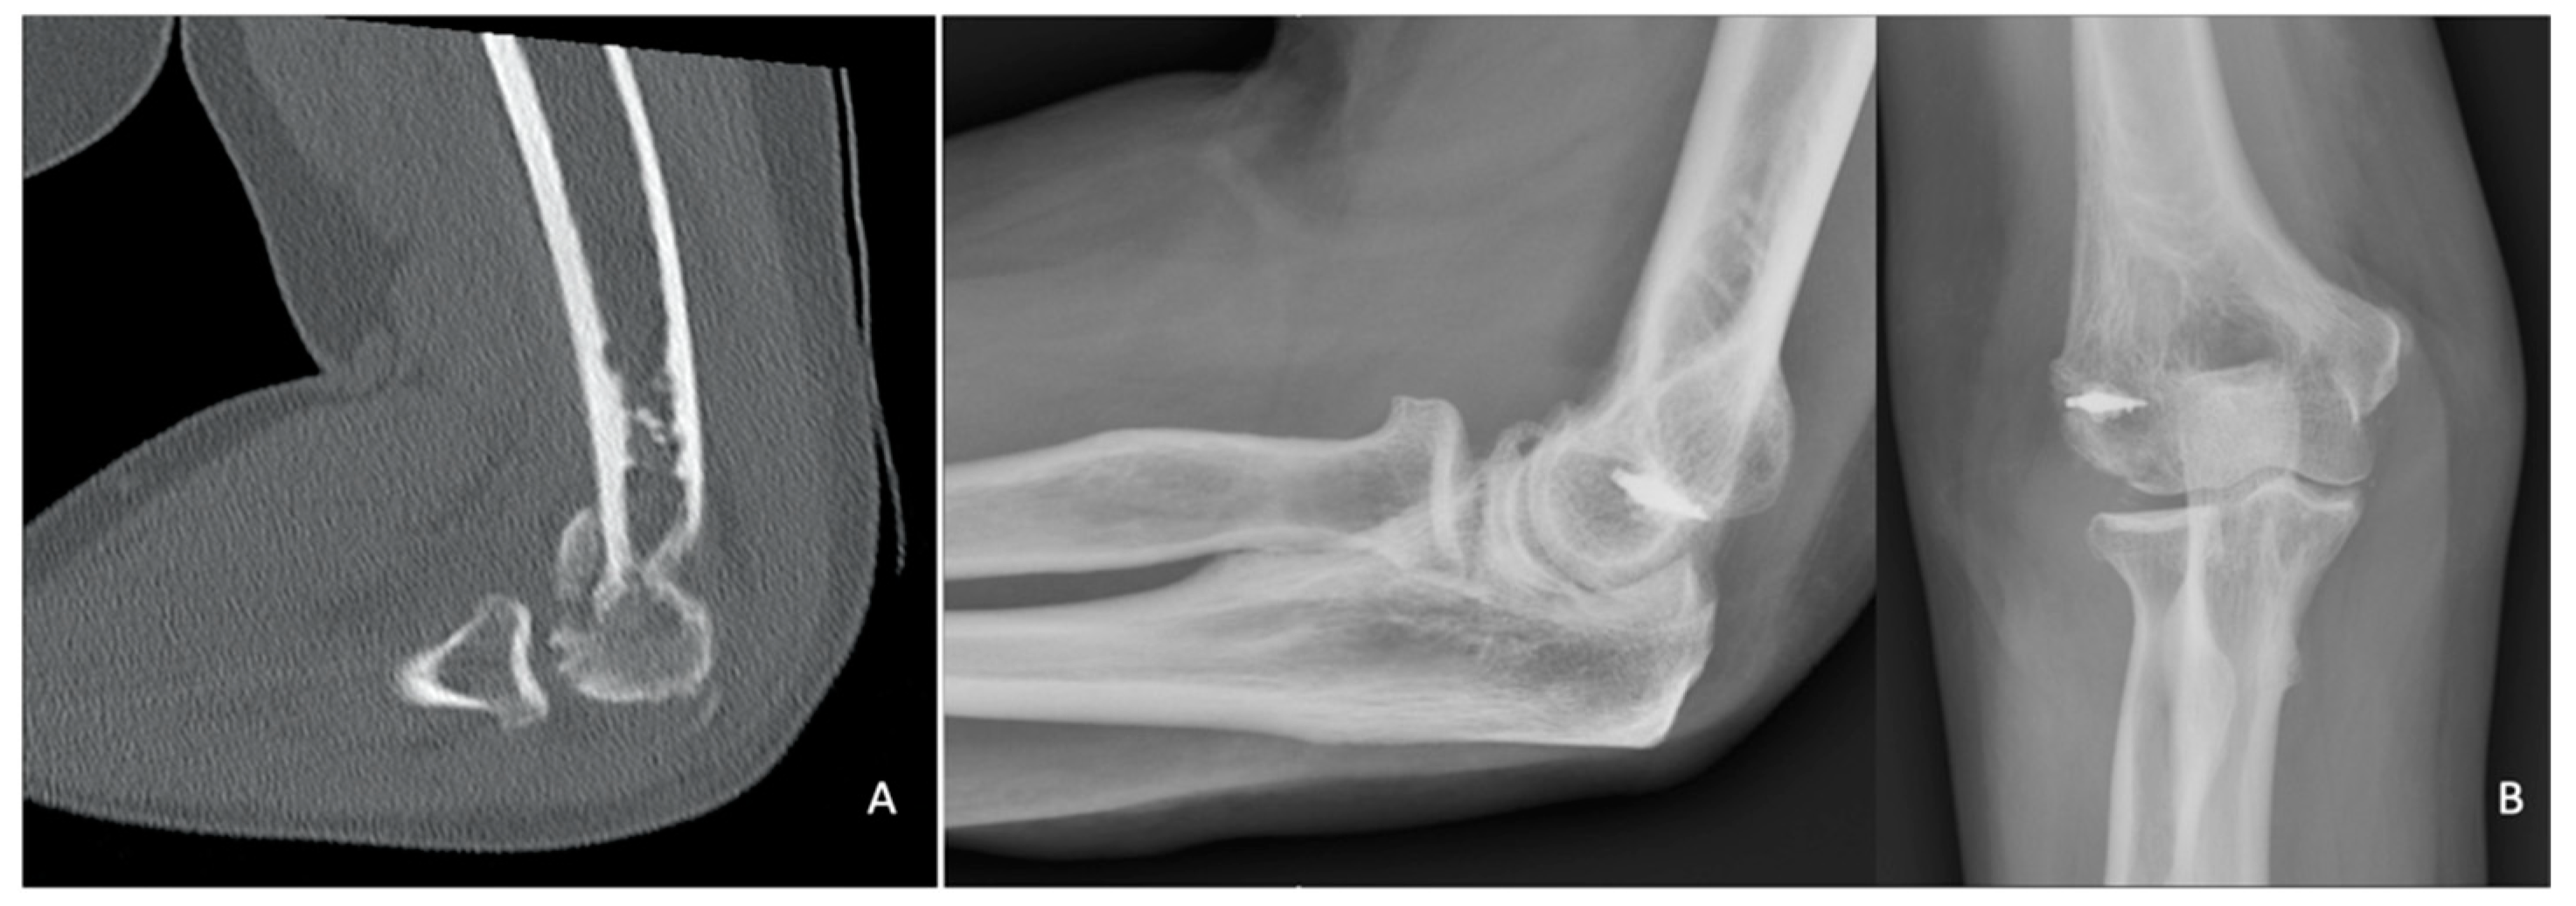

2. Classification

3. Imaging